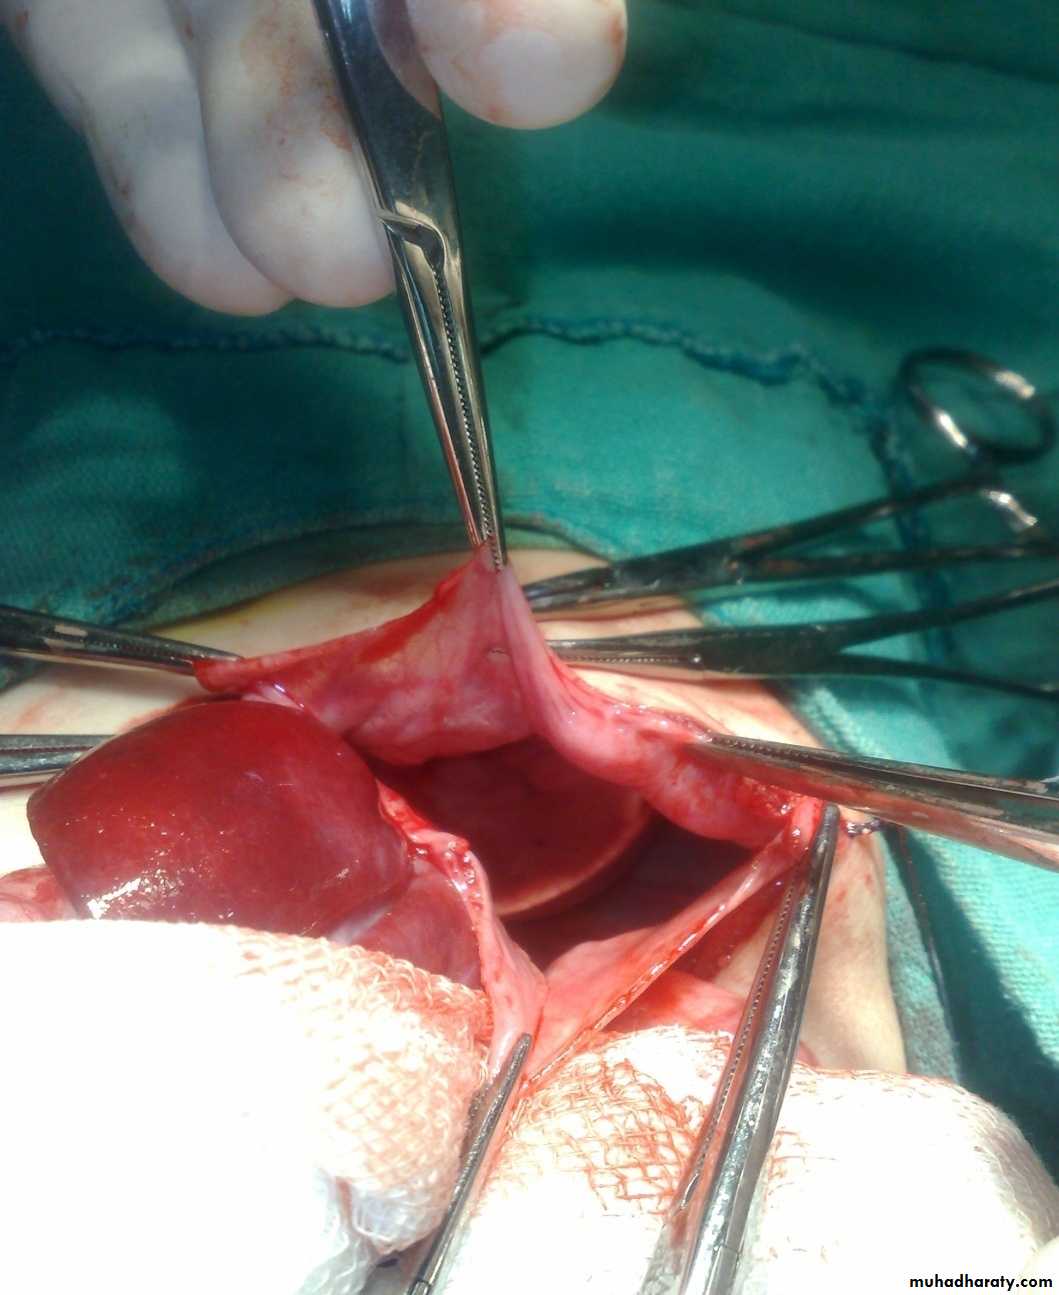

Subcostal incision

Defect=sac